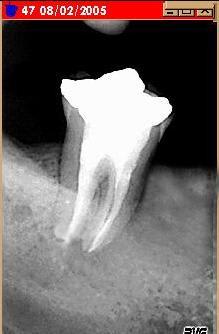

bon, comme je suis un peu tetu et ne me laisse pas faire aussi facilement par une dent à la con : curetage maison par voie "pochstique".

Curetage feu6le - Eugenol

résultat.

j'attend encore un peu pour le bridge.

En bonne voie iaqf7p - Eugenol

et bientot.

Miracle whpizr - Eugenol